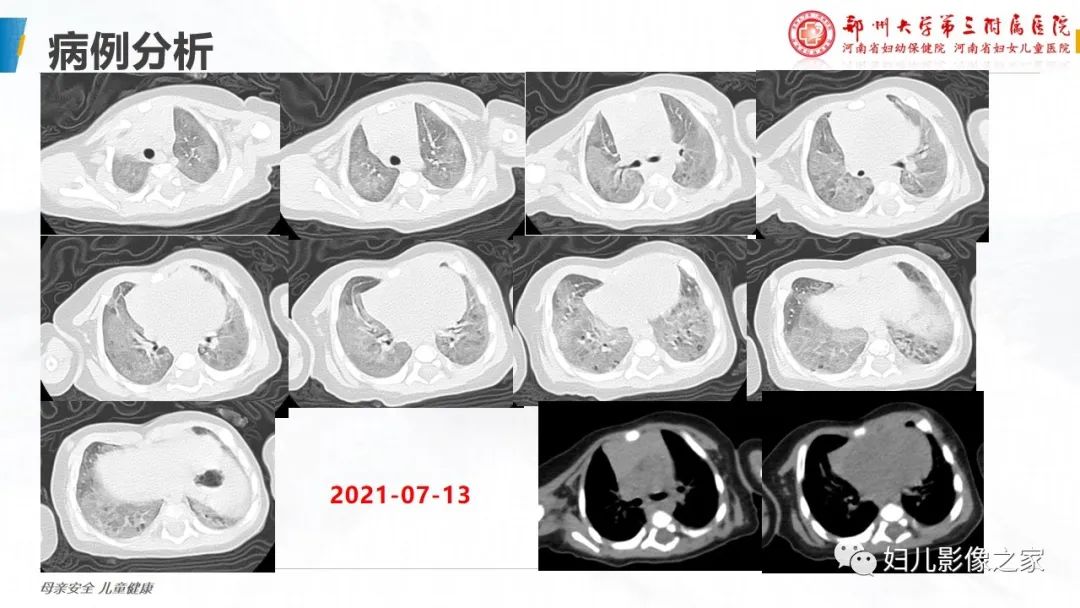

【PPT】肺泡蛋白沉积症的影像诊断-6